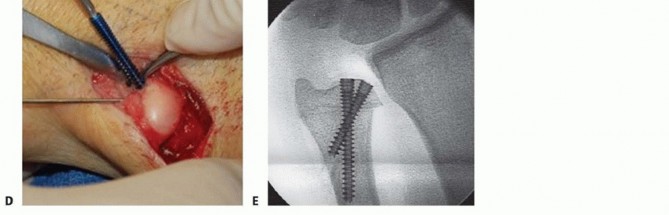

FIG 4 • Ulnar impaction syndrome in a 73-year-old woman after distal radius fracture nonunion and subsequent collapse. She underwent open reduction and internal fixation of the radius fracture as well as ulnar shortening osteotomy to correct the posttraumatic ulnar positive variance. Severe osteopenia prevented stable fixation of the ulnar osteotomy with the standard plate and necessitated a longer eight-hole DCP.